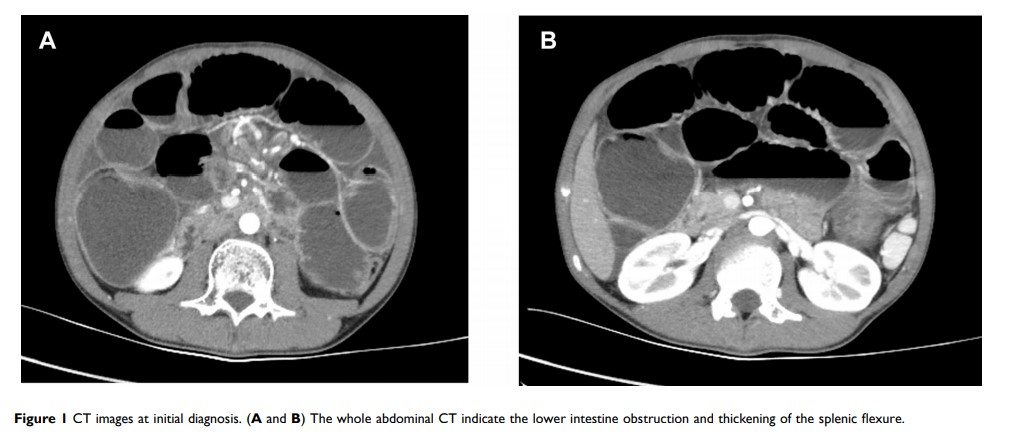

小儿 MYH 基因相关性侵袭性大肠癌的新型突变:一个病例报告和文献综述